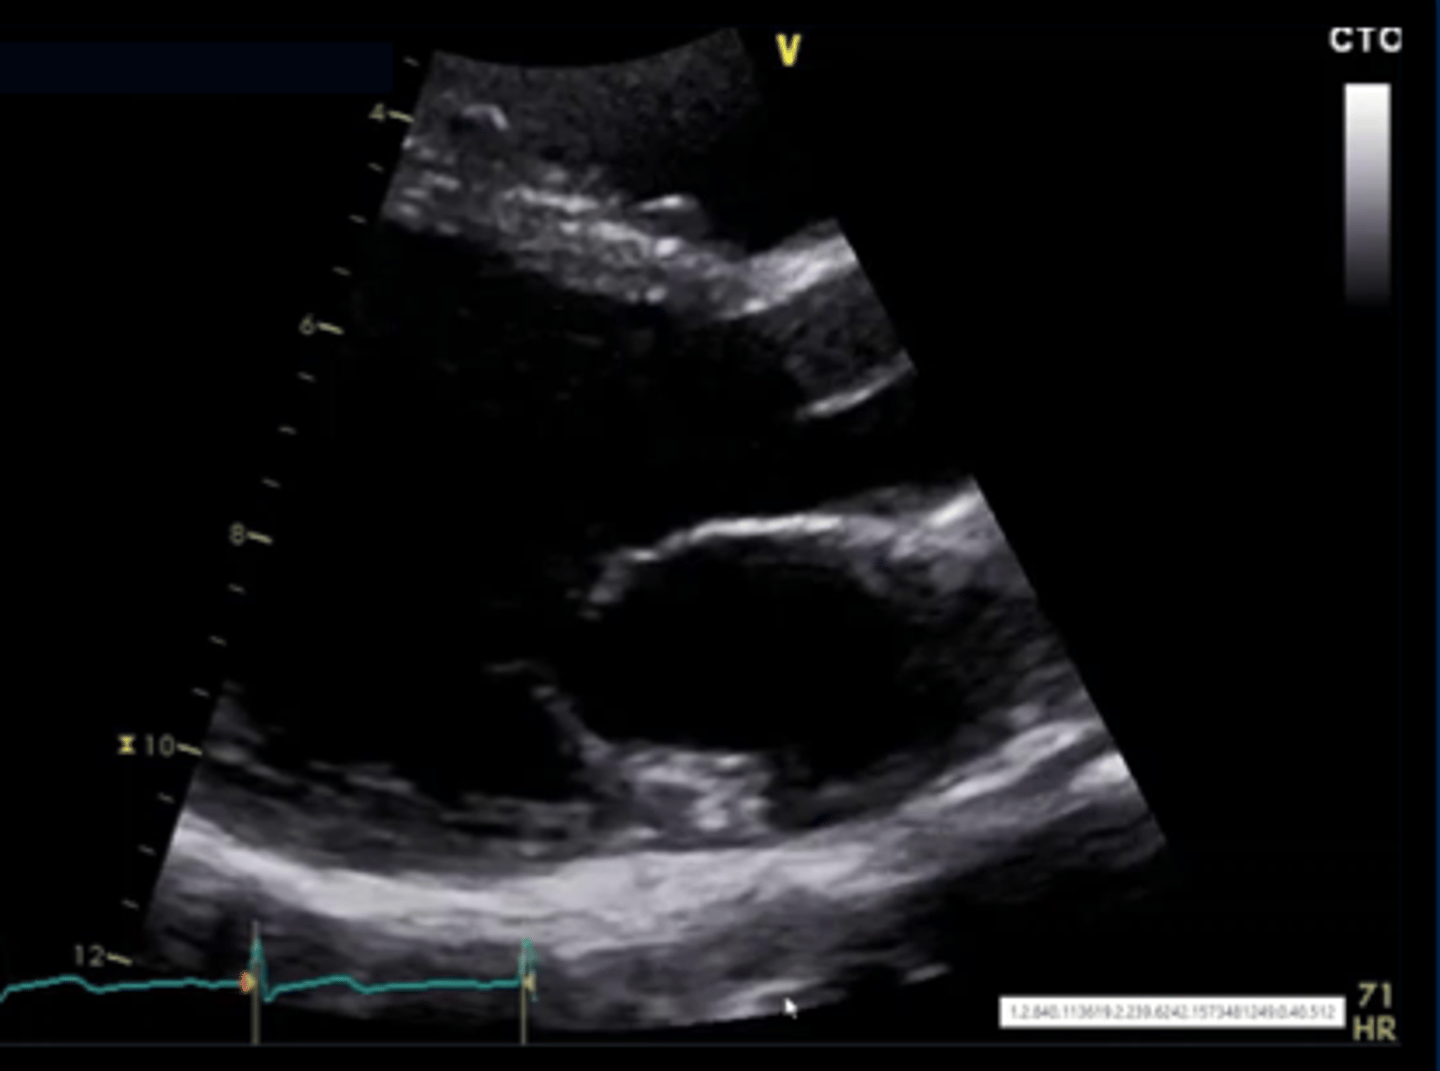

anterior mitral valve leaflet

top leaflet

posterior mitral valve leaflet

bottom leaflet